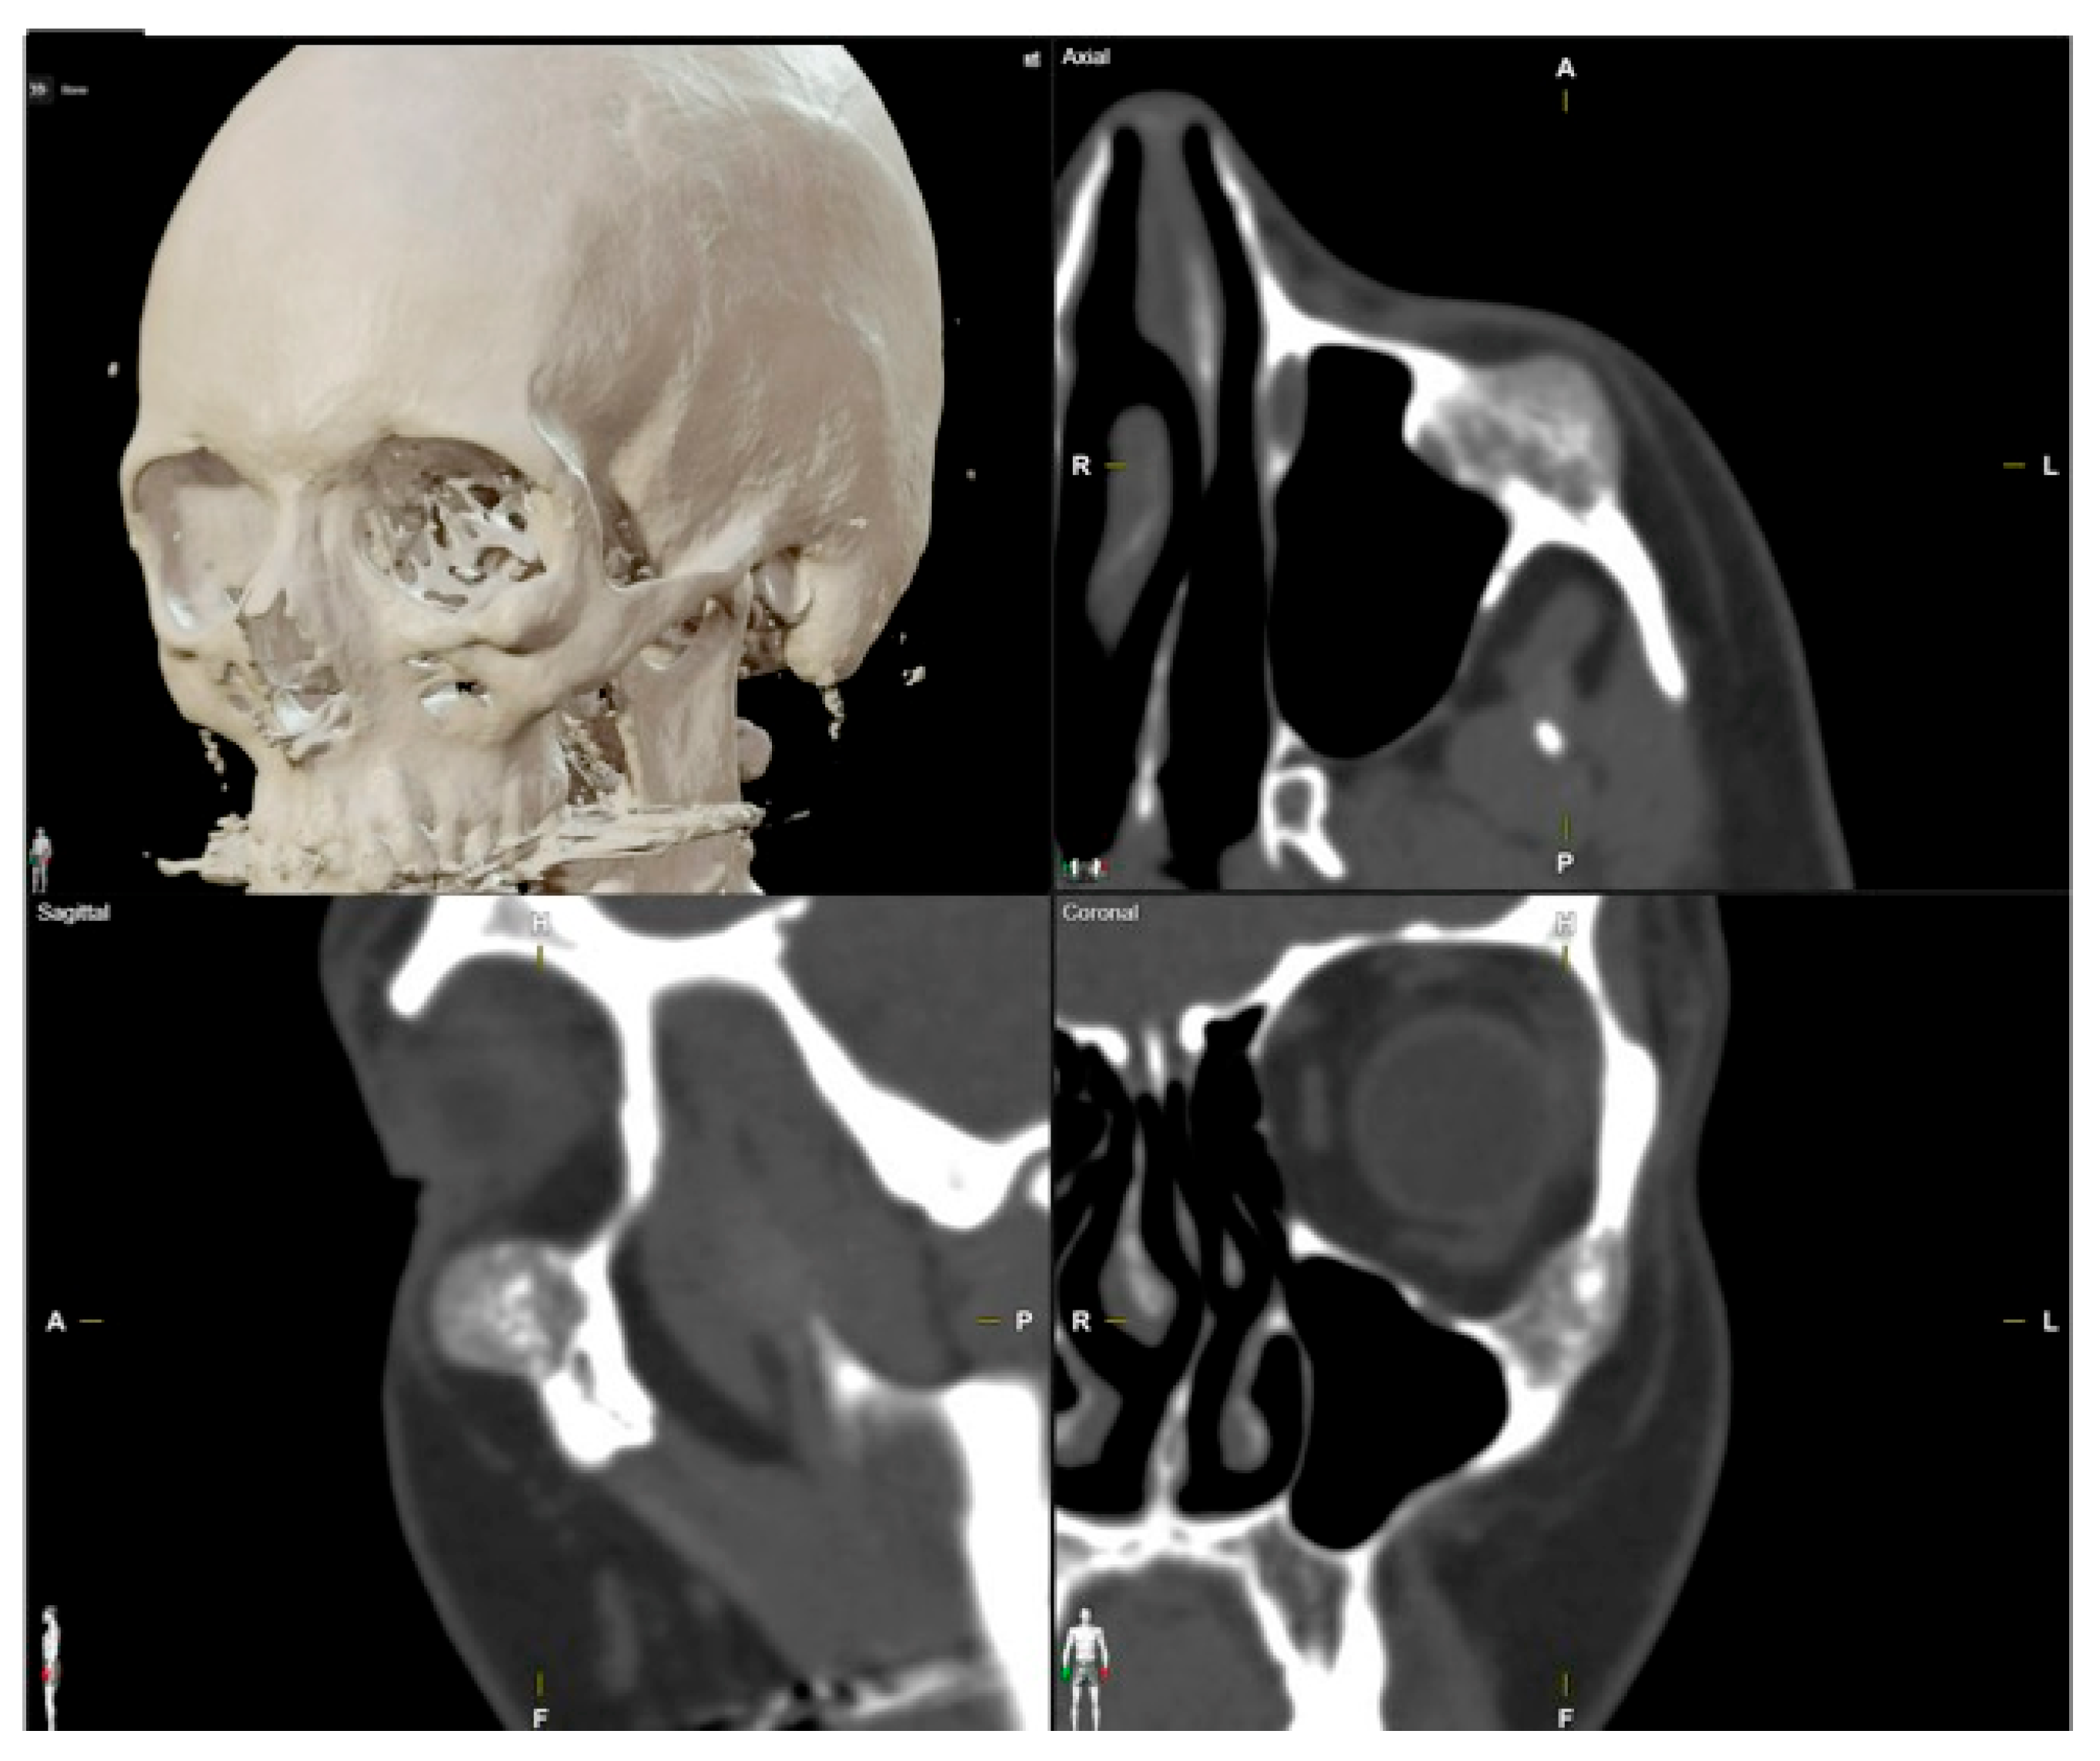

| 1 | 53/F | L/25 mm | Y | 4 mo | Dystopia | N | CT, MRI | Supraorbital rim, orbital roof | Intraosseous venous malformation | - | Resection + reconstruction | Y | Y | 1st, 2nd, 3rd | Coronal | Y | Piezoelectric device | N | PEEK prosthesis | 7 y/N |

| 2 | 54/F | R/33 mm | Y | 9 y | N | Y | CT, MRI | Frontal bone, orbital roof | Intraosseous venous malformation | - | Resection + reconstruction | Y | Y | 1st, 2nd, 3rd | Coronal | Y | Piezoelectric device | N | PEEK prosthesis | 6 y/N |

| 3 | 36/F | L/19 mm | Y | 6 mo | N | N | CT, MRI | Zygoma | Arteriovenous malformation | - | Resection + reconstruction | Y | Y | 1st, 2nd, 3rd | Transconjunctival + blepharoplasty + maxillary vestibular | Y | Piezoelectric device | N | PEEK prosthesis | 5 y/N |

| 4 | 47/M | L/30 mm | N | 2 y | N | N | CT | Zygoma | Intraosseous venous malformation | - | Resection + reconstruction | Y | Y | 1st, 2nd, 3rd | Transconjunctival + lateral canthotomy + maxillary vestibular | Y | Piezoelectric device | N | PEEK prosthesis | 6 y/N |